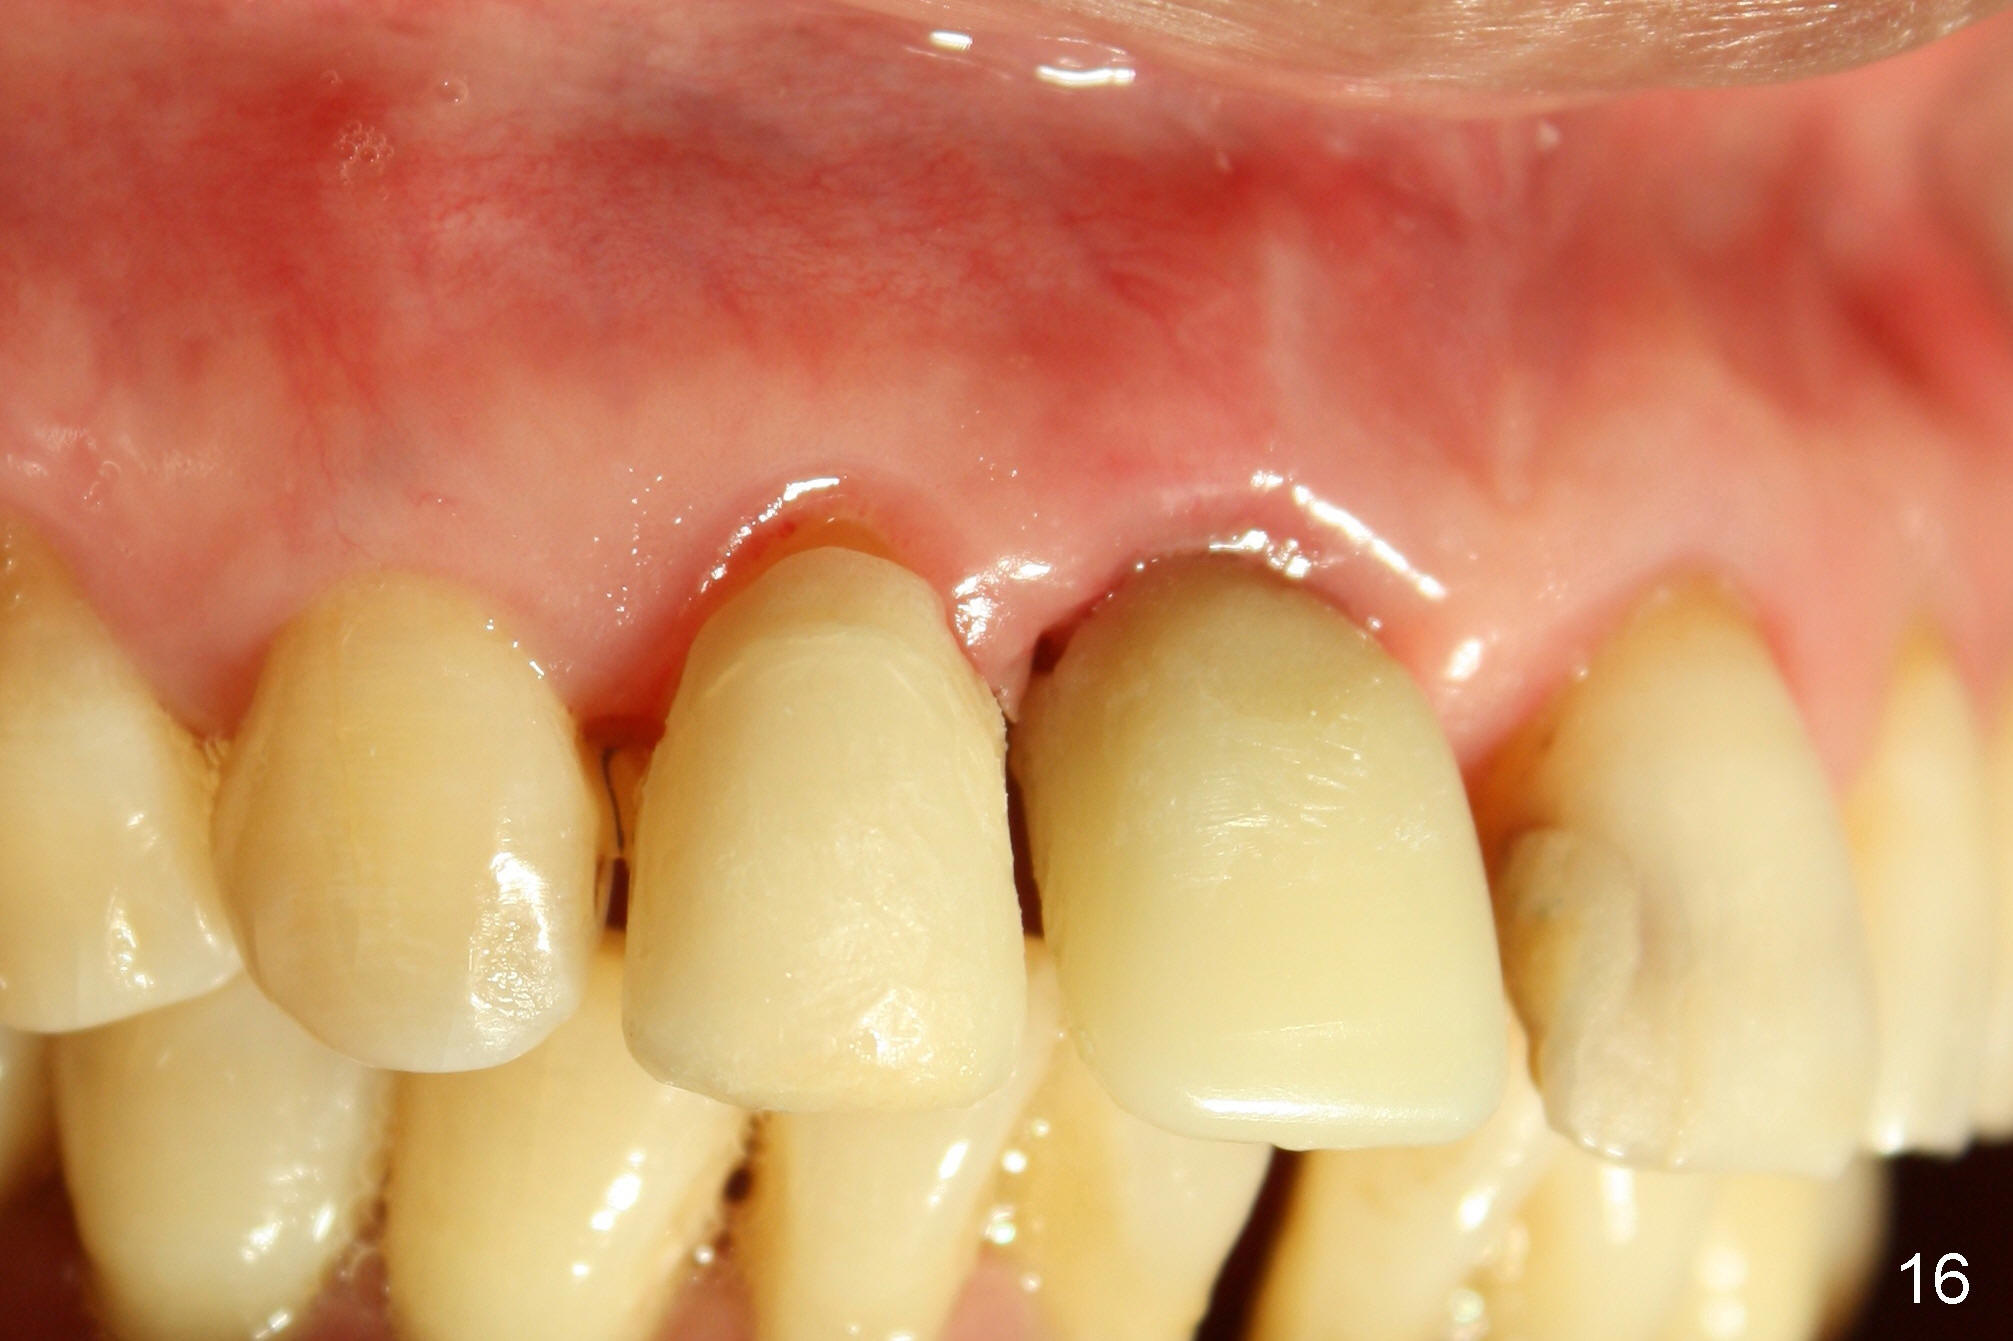

The patient returns for follow up 8 days postop and the labial margin of the provisional looks long. The metal crown is changed to a provisional at the visit. Eight days later, the provisional at the site of #8 is removed for labial margin trimming; the labial gingiva heals (Fig.14 *). The labial plate remains slightly convex (Fig.15). The labial margin of the provisional at the site of #8 is at the same level of that of #9.

Four-month follow up shows that bone graft from the tuberosity appears to have healed with the implant microthreads (Fig.17 *); there is a diastema between #8 and 9 (arrowheads). Before removal of the provisionals of #7 and 8 for final impression, new composite is added to the mesial surface of #9 as the first step of closure of the diastema (Fig.18 <).

One year post cementation, there is cortical bone formation mesial to the implant (Fig.19 <). Buccal concavity is minimal (Fig.20).